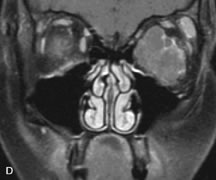

Inflammatory and Lymphoproliferative Lesions

Inflammatory conditions of the orbit, both idiopathic (inflammatory pseudotumor) and those of known causes, have been found to be hypointense to fat and isointense to muscle on Tl-weighted studies and isointense or slightly hyperintense to fat on T2-weighted images (Fig. 21).50,64,69 The more fibrous or sclerosing varieties have less signal intensity on T2-weighted images. Marked enhancement is seen in pseudotumor infiltrates after gadolinium administration.70 The same signal characteristics are demonstrated in patients with Tolosa-Hunt syndrome, with mass lesions seen in the cavernous sinuses and orbital apices.71

Fig. 21. A. T1-weighted MR scan demonstrates diffuse enlargement of both the superior rectus and levator palpebrae superioris muscles (single arrows). The involvement of the tendinous insertions and preseptal soft tissues (open arrows) as well as lack of involvement of other muscles helps differentiate this entity from thyroid-associated orbitopathy. B and C. Postcontrast fat-suppressed T1-weighted MR scans demonstrate extensive enhancement of the involved muscles as well as the preseptal (open arrows) and perinuscular tissues (double arrows).